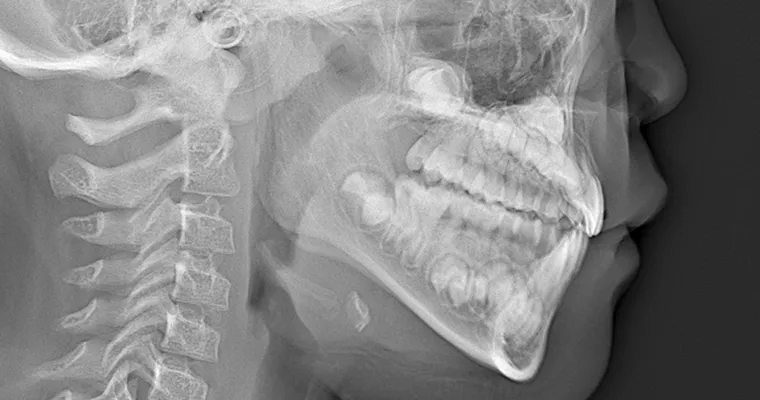

治療前 パノラマレントゲン

治療前 セファロレントゲン